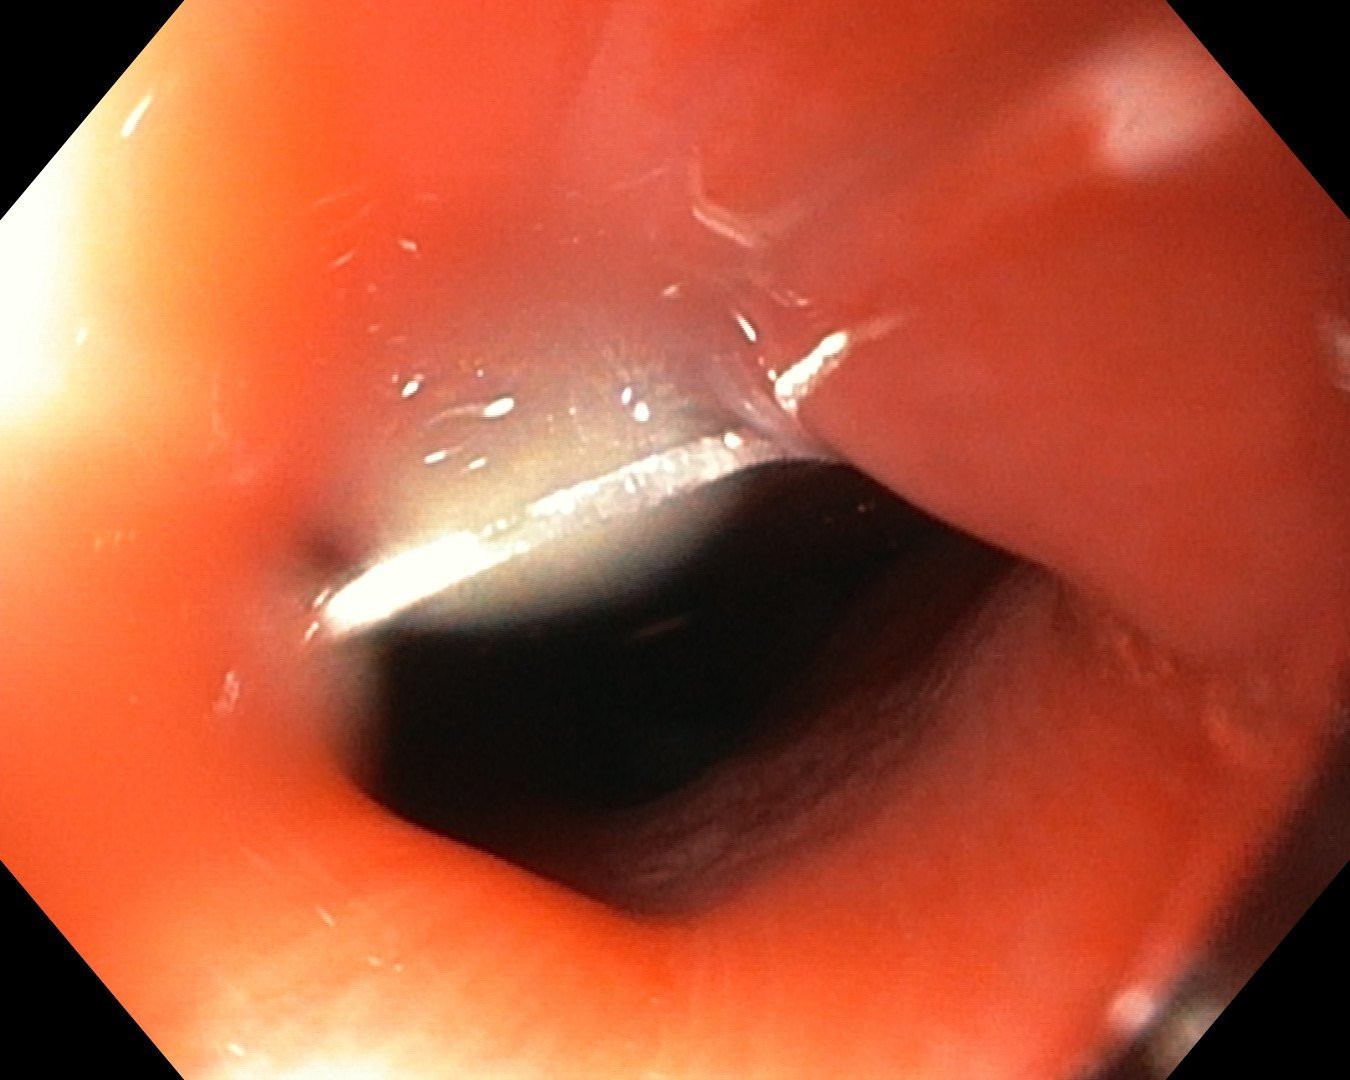

Cùng ngày, Bệnh viện Đa khoa Xuyên Á cho biết, tại đây cũng vừa tiếp nhận cấp cứu gắp dị vật là mảnh kim loại tròn, kích thước 17mm kẹt ở vùng hạ họng của bé trai T.P.T. (30 tháng tuổi, ngụ tại tỉnh Đồng Tháp). Trước đó, bệnh nhi đã ngậm mảnh kim loại trong miệng, khi chơi đùa đã vô thức nuốt dị vật, ngay lập tức trẻ rơi vào tình trạng khó thở, đau ở vùng họng, nôn ói.

Bằng phương pháp nội soi, các bác sĩ đã lấy thành công dị vật ra ngoài. Tuy nhiên, mảnh kim loại sắc nhọn đã gây tổn thương thực quản, phải tiếp tục theo dõi, điều trị để tránh nguy cơ biến chứng có thể xảy ra.

| Dị vật là mảnh kim loại gây tổn thương thực quản cho bé trai 30 tháng tuổi |